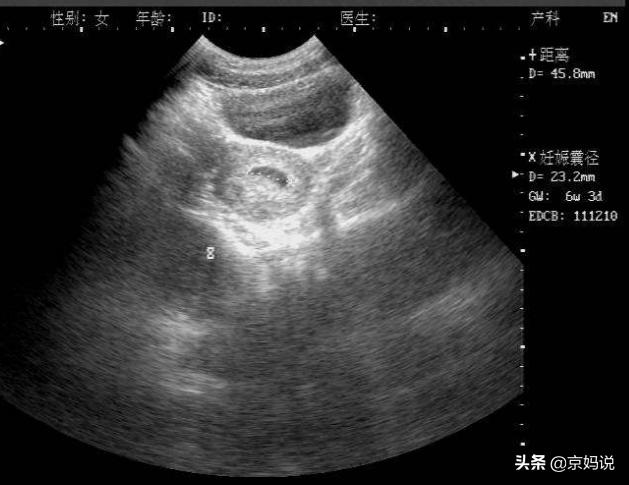

有网友问:怀孕6周时检查,胎心正常,等怀孕10周再去检查额时候,没有胎心,胎芽小,这样的情况,确定是胎停吗?如果10周做B超,显示没有胎心、胎芽小,应该就是胎停了。

因为到孕10周的时候,胚胎应该不小了,相比6周,胎芽应该是变大的;而且之前6周有胎心,说明胎儿在6周前发育的很好,但现在10周没有胎心了,那应该是胎儿停止发育了。建议咨询医生,遵医嘱应对就好。

发生胎停,多是因为胚胎本身质量不好,属于“优胜劣汰”的自然过程,大多数发生在怀孕10周之前,而且大部分是没有胎心。